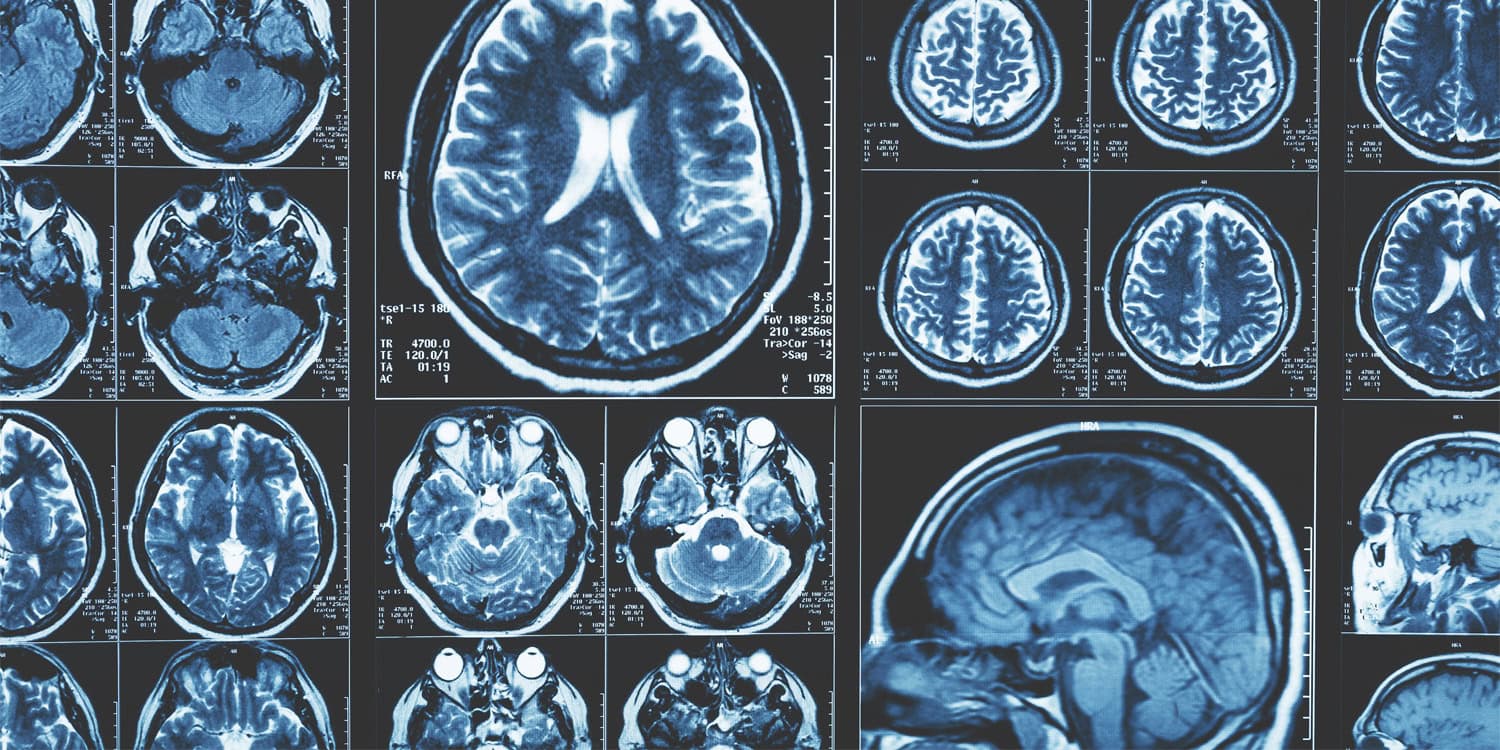

Для столь шокирующих открытий были проанализированы 2 603 магнитно-резонансных снимков взрослых людей в возрасте от 30 до 97 лет. Брали данные из двух независимых источников для чистоты эксперимента. Учёные тщательно измеряли, как изменяются расстояния между симметричными областями мозга в левых и правых полушариях: например, насколько с годами расходятся левый и правый гиппокамп, и что при этом делают другие важные структурные зоны.